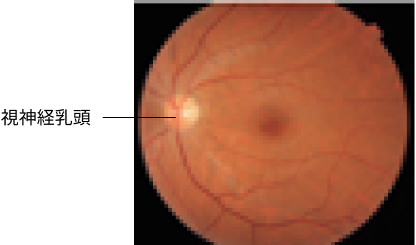

眼底検査

眼底鏡やカメラを用いて、眼の奥の網膜や視神経に異常が起こっていないかを調べます。

正常な眼の眼底写真

日本眼科医会

(https://www.gankaikai.or.jp/info/

funduscopy.pdf)(2024年7月閲覧)